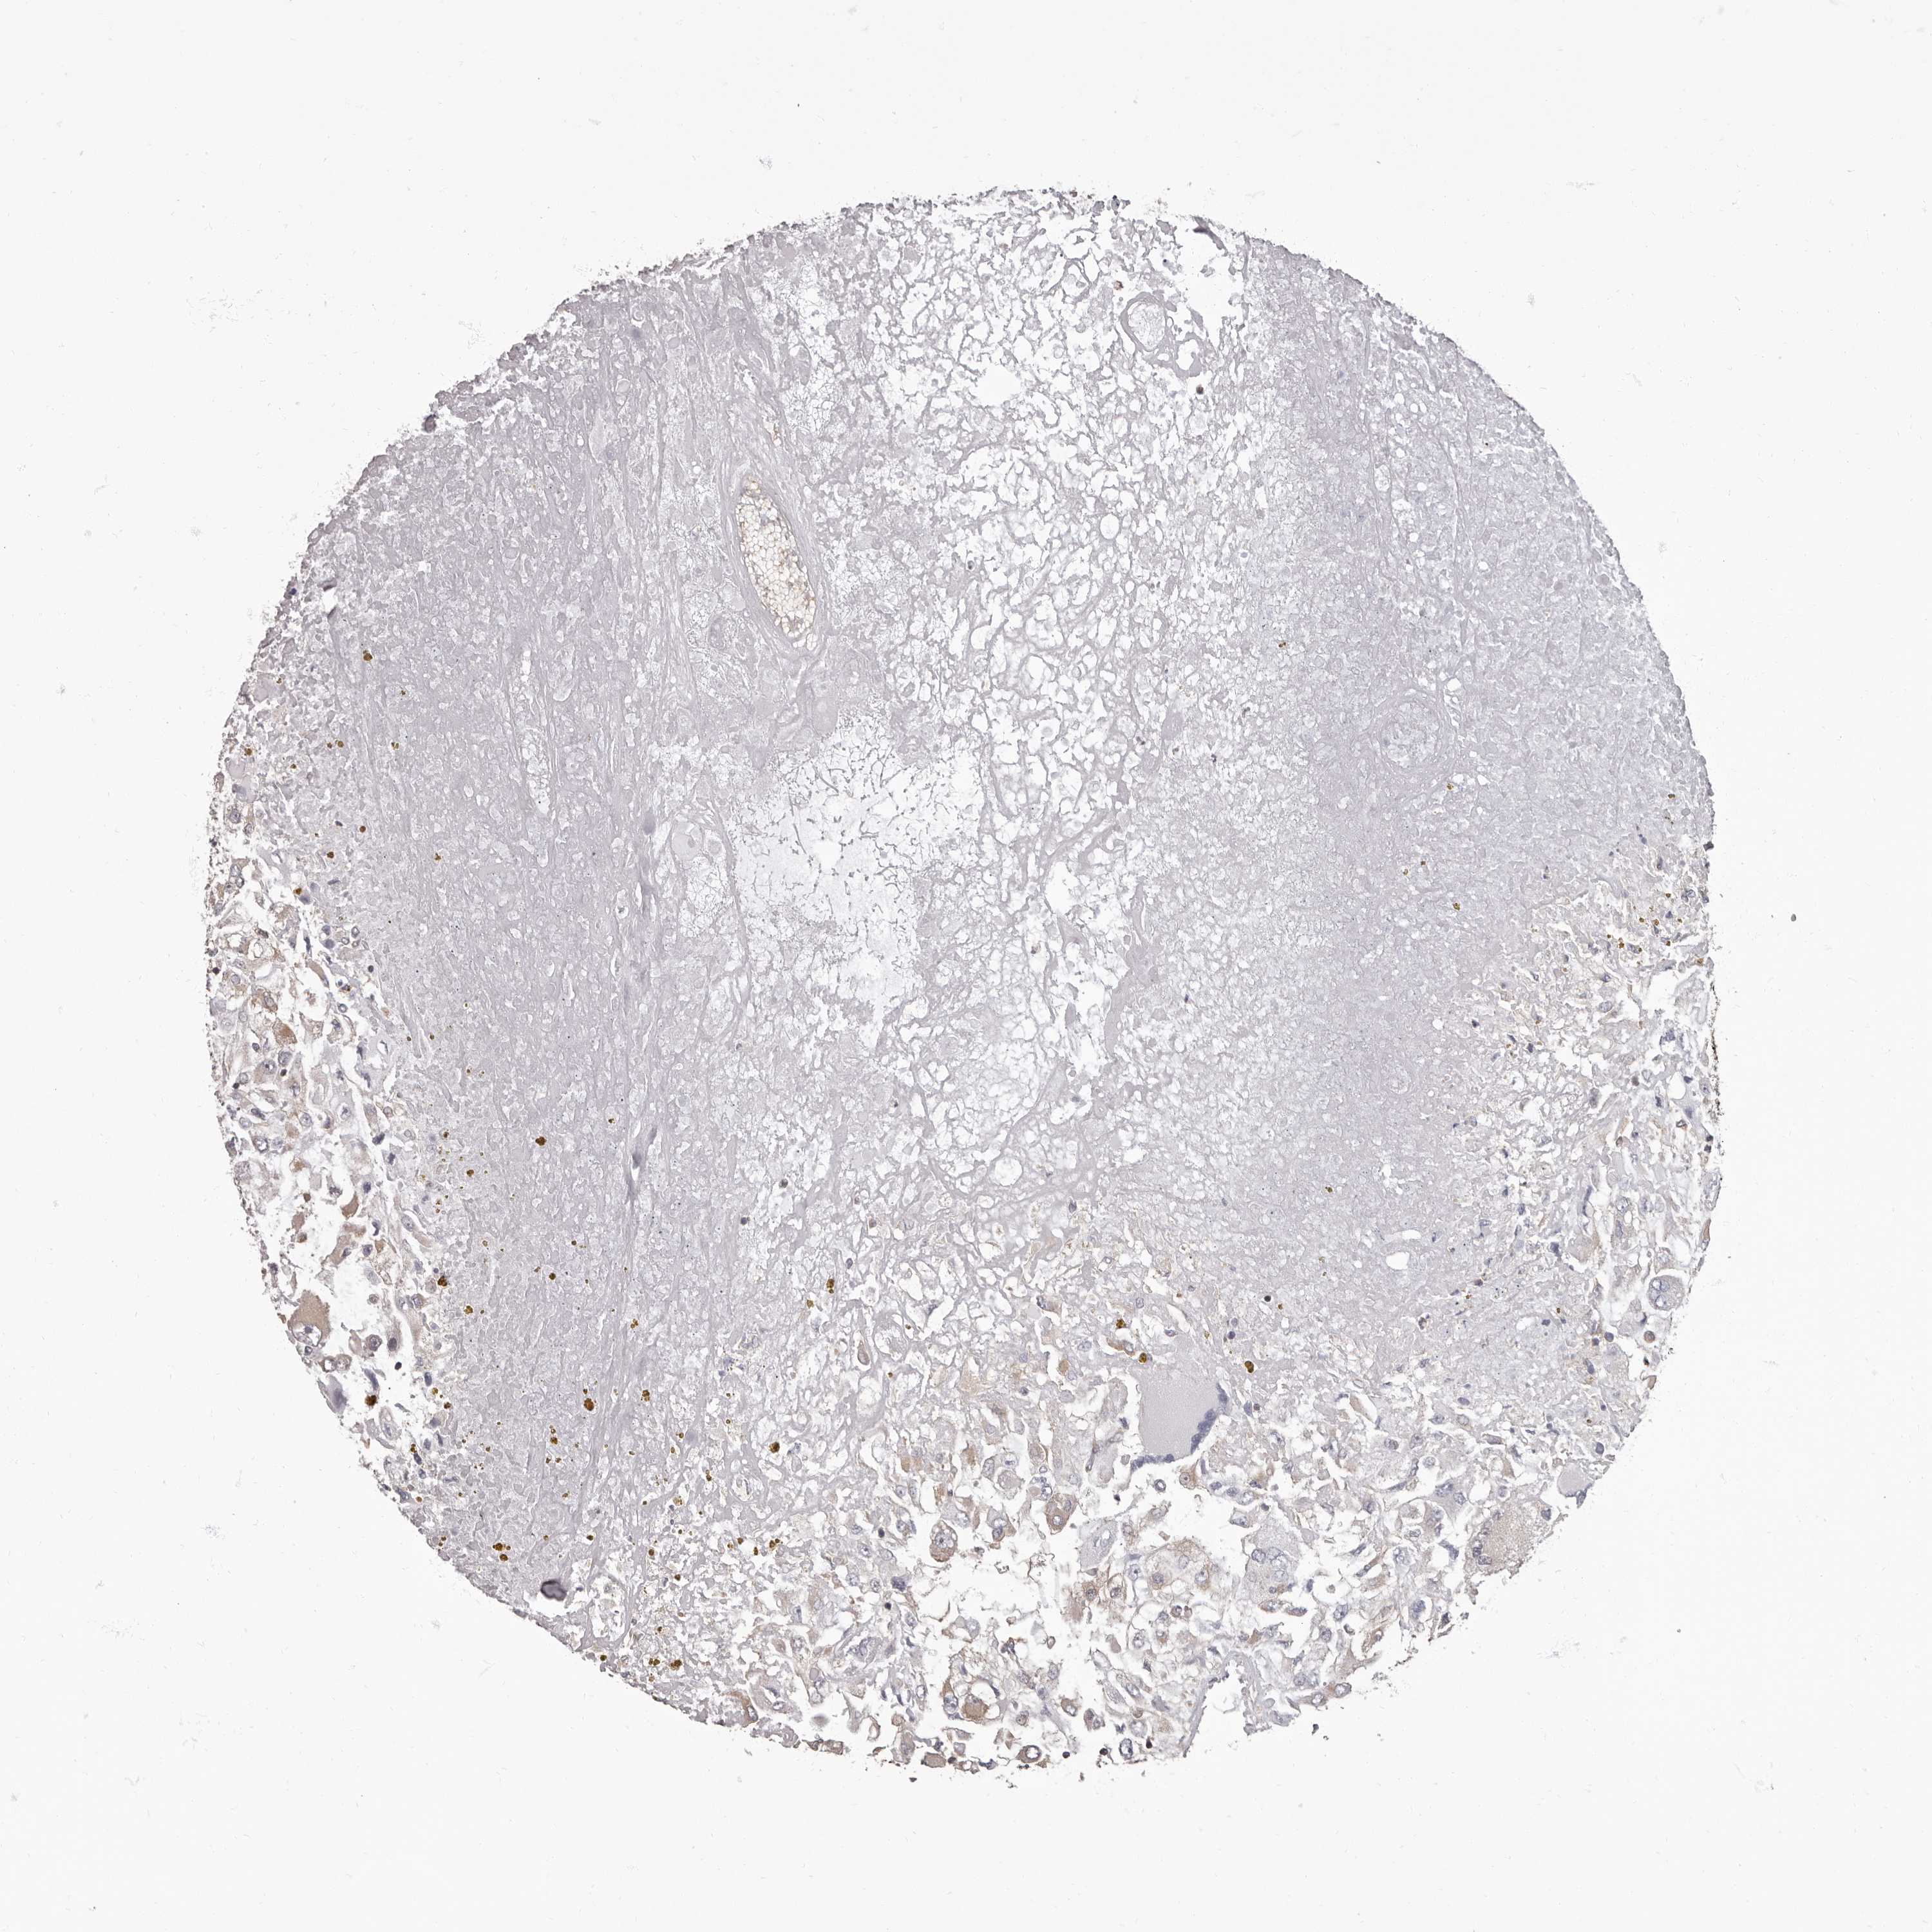

CANCER RENAL CANCER Show tissue menu

KICH TCGA KIRC TCGA KIRC VALIDATION KIRP TCGA PROTEIN RCC CPTAC PROTEIN EXPRESSION